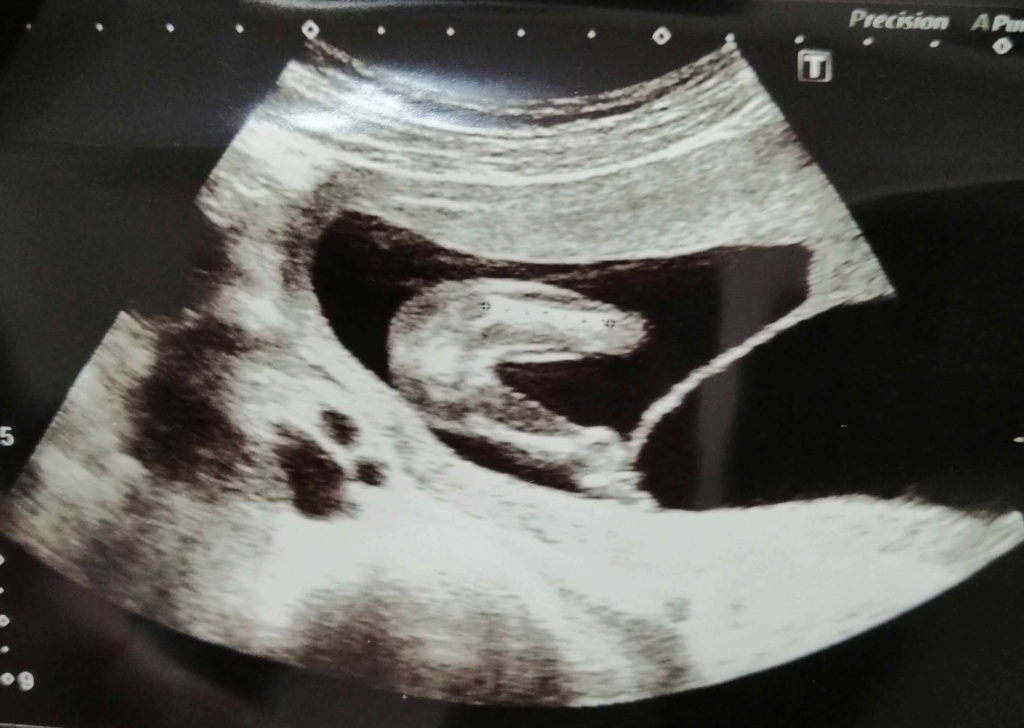

◆エコー

私が双子妊娠5ヶ月(16週)の時の赤ちゃんのエコーです。

2人揃ってエコーに映ることが出来るのは5•6ヶ月頃までですので2人がしっかりと写っている良い写真を撮ってもらいましょう。

顔つきが人間らしくなり、大きくなってきています。

5ヶ月は性別も判明する頃です。医師から上の画像を見て「女の子かもね!」と言われました。